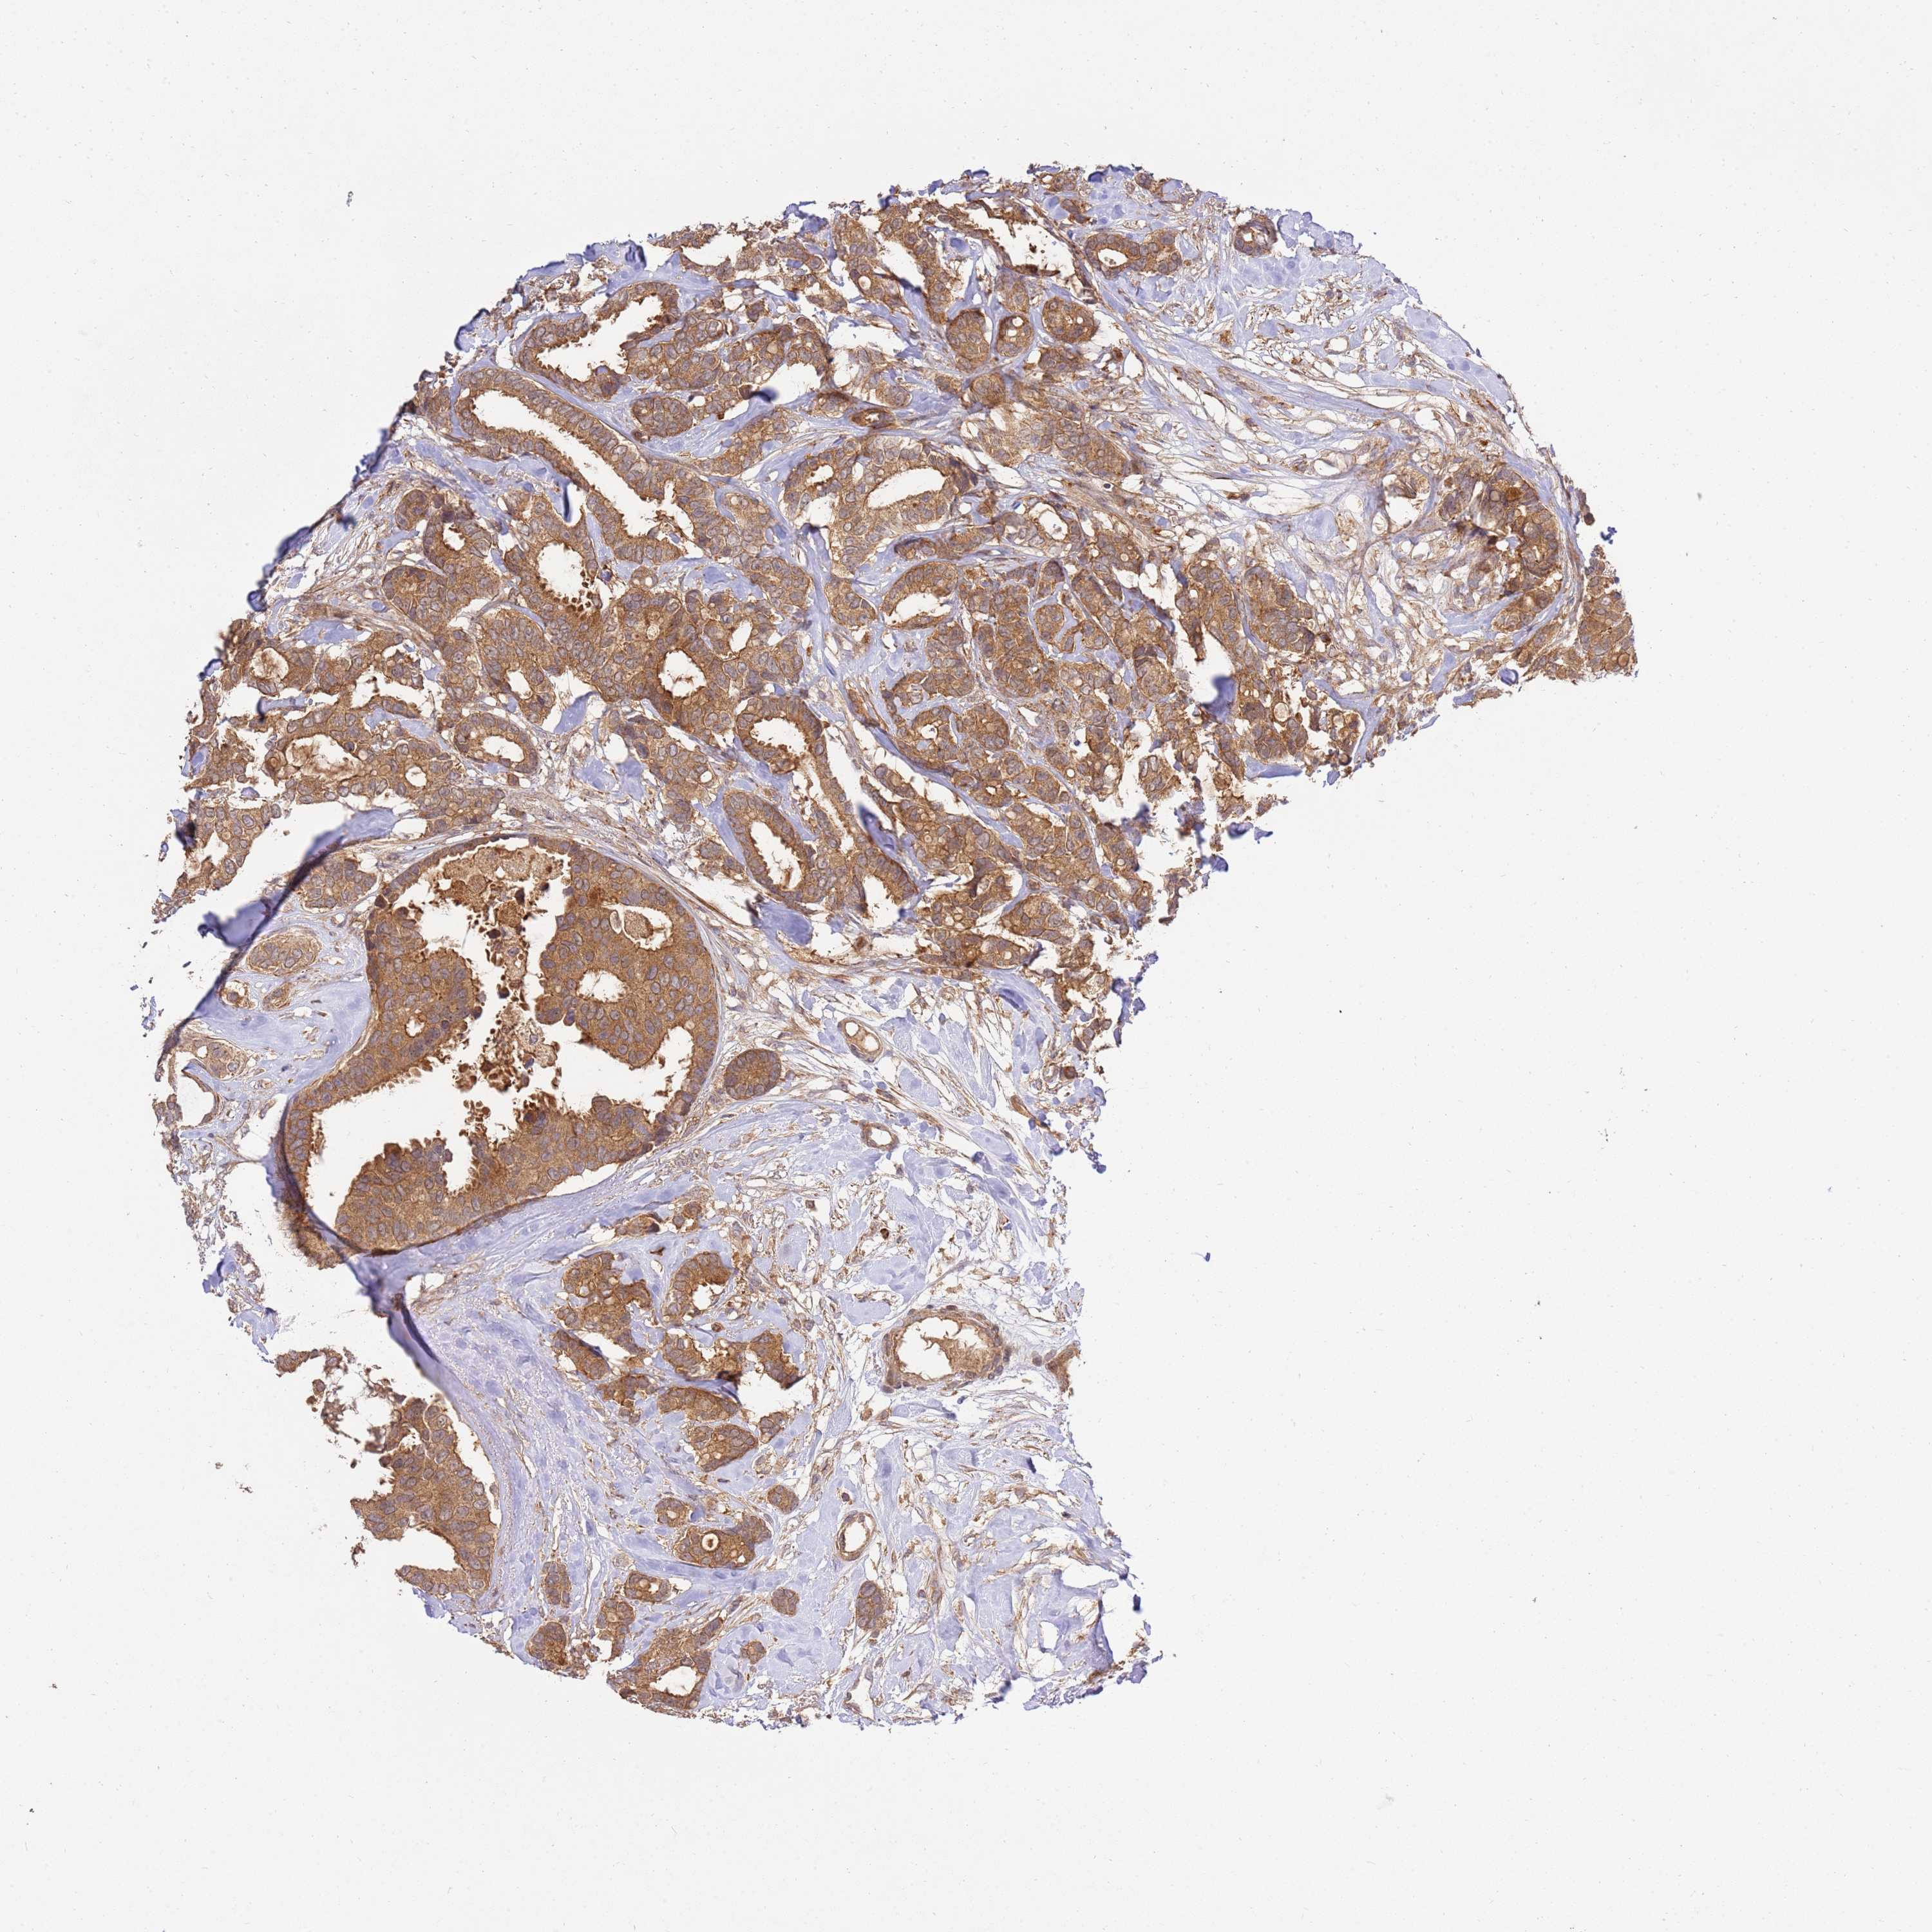

BRCA TCGA BRCA VALIDATION PROTEIN EXPRESSION

ANTIBODIES

AND

VALIDATION